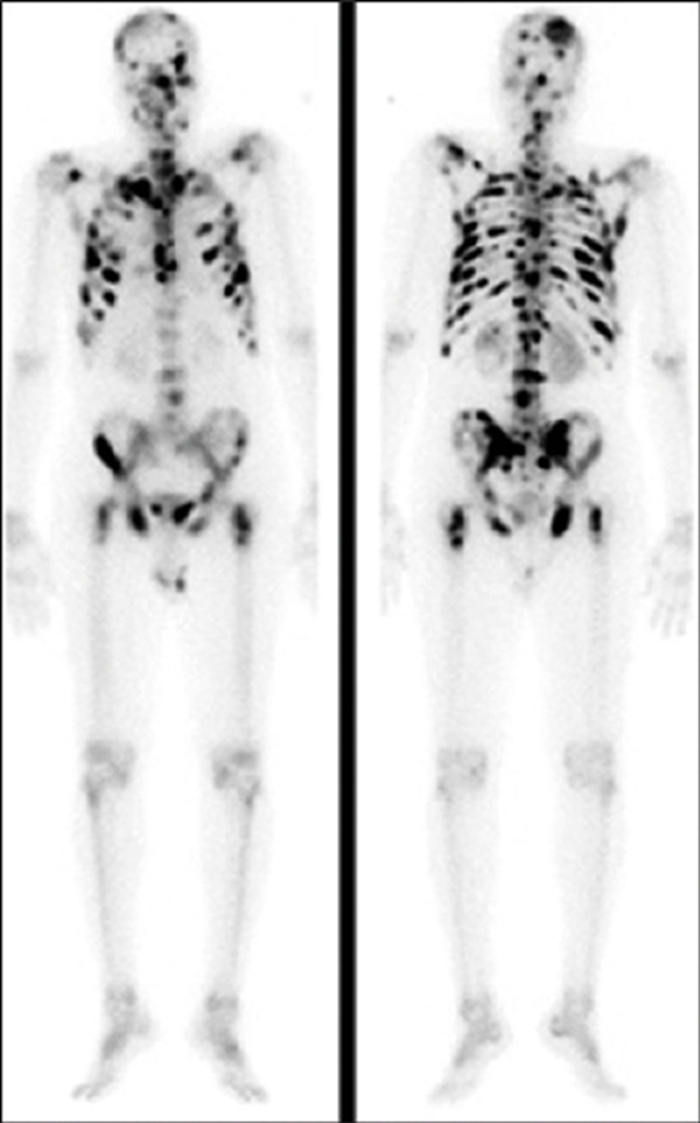

what is used to look for bony metastasis in prostate cancer?

A

An isotope bone scan (also called a radionuclide scan or bone scintigraphy) can be used to look for bony metastasis.

A radioactive isotope is given by intravenous injection, followed by a short wait (2-3 hours) to allow the bones to take up the isotope.

A gamma camera is used to take pictures of the entire skeleton.

Metastatic bone lesions take up more of the isotope, making them stand out on the scan.